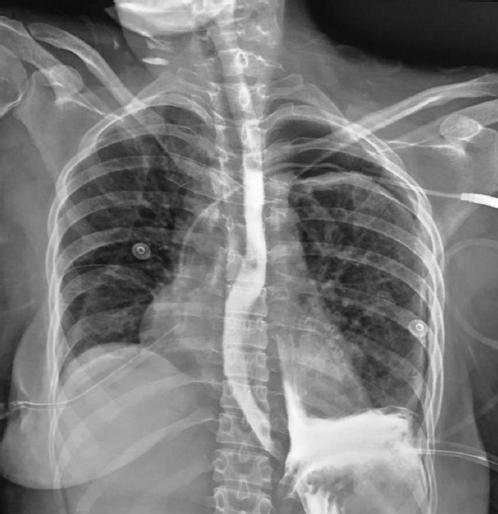

El hemograma mostró leucocitosis ligera con neutrofilia. La radiografía de tórax reveló radioopacidad en masa en los dos tercios inferiores del hemitórax izquierdo, con desplazamiento ligero de las estructuras de la línea media y ensanchamiento de los espacios intercostales. No se constataron signos de neumomediastino.

La paciente llega al hospital con 10 días de evolución, ventilando espontáneamente, con SO2 del 94%, con sonda de Levine y Foley, leucocitosis moderada de 18,5 × 109/l con marcada neutrofilia (85%) y reactantes de fase aguda elevados considerablemente, y presentando un pico febril vespertino de 39 °C.

Se le realiza una tomografía computarizada de tórax con contraste oral que corrobora la presencia de perforación a nivel del tercio inferior del esófago, con comunicación directa con la cavidad torácica izquierda, sin extravasación hacia el mediastino.

El esofagograma por fluoroscopia informa trayecto que comunica con la cavidad pleural a aproximadamente 2.7 cm por encima de la unión esofagogástrica, que mide 2 cm de longitud, en relación con fístula esofagopleural (Fig. 1).

Figura 1 Esofagograma por fluoroscopia en el que se visualiza la salida de contraste desde el tercio inferior del esófago hacia la cavidad torácica.